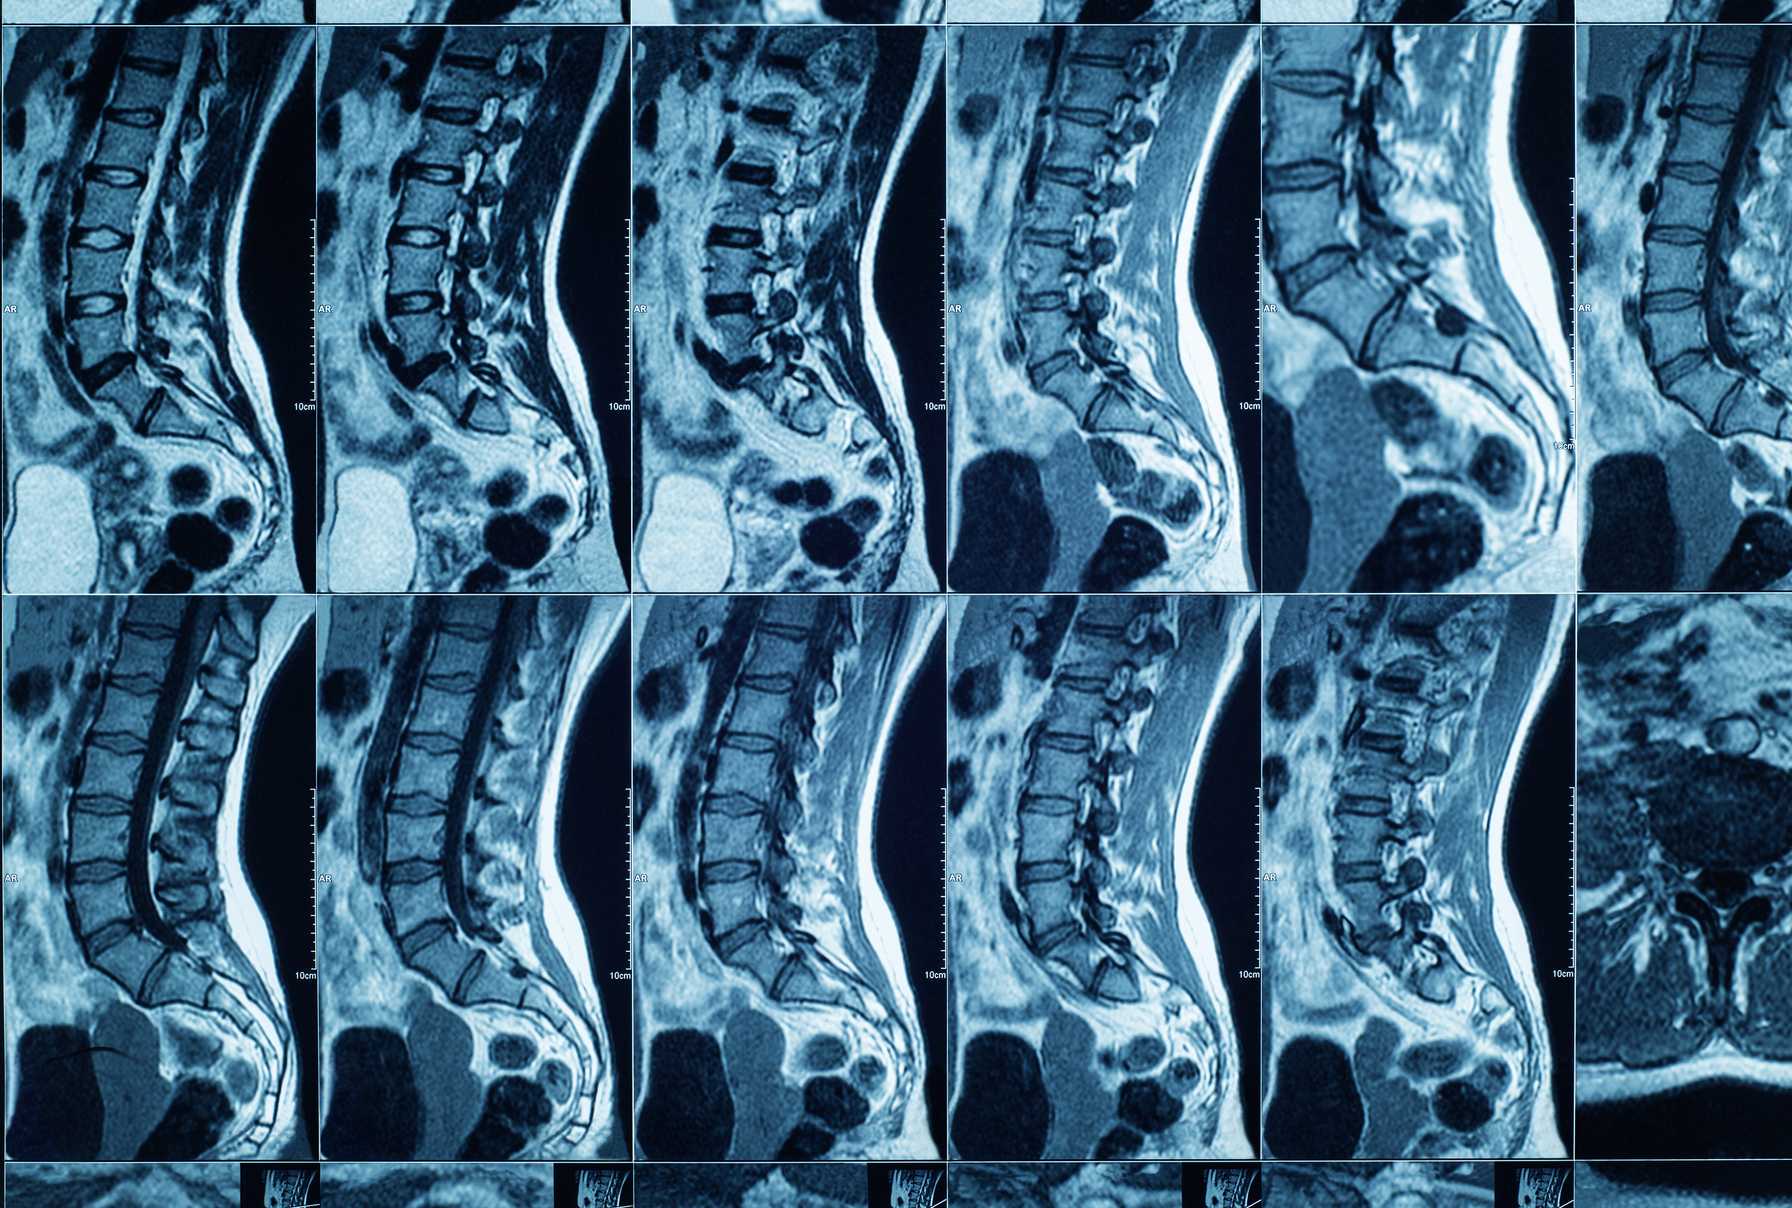

The Leo M. Davidoff Department of Neurological Surgery is driven by a mission to provide comprehensive, multidisciplinary care for patients with disorders affecting the nervous system, including the brain, spinal cord and peripheral nerves. Each service within the department endeavors to optimize the patient journey using a patient-centered approach, to engage in high-impact translational research and to provide exceptional education and mentorship of students, residents, fellows and faculty.